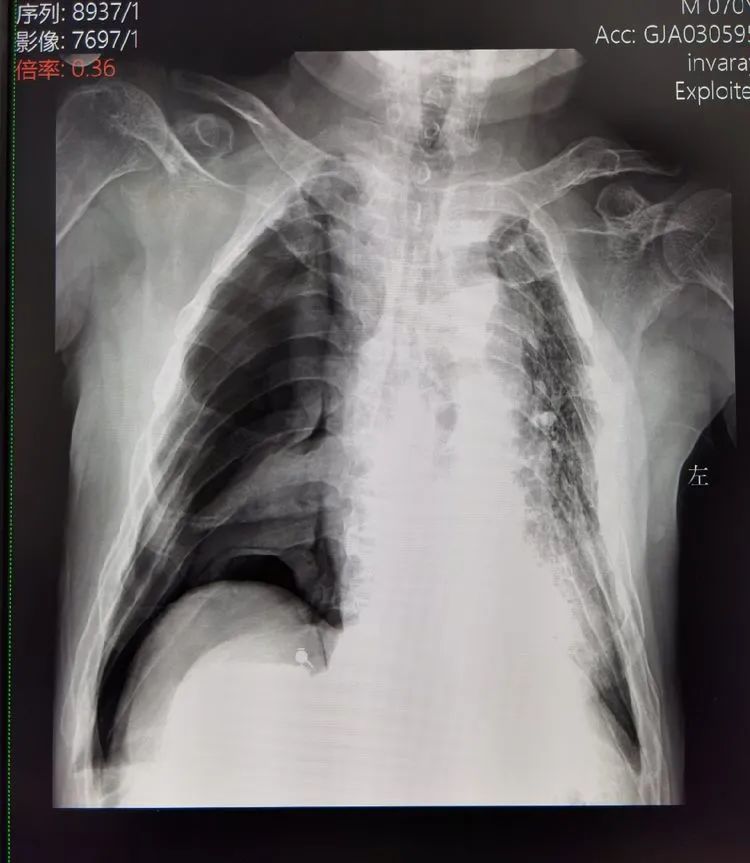

“胸闷、胸痛,对。好好的胸右边就突然疼起来了,一直疼。我们年纪大走路不方便,谁知道歇也没有歇过来,实在不行赶紧来了......”就诊的是家住谢区的唐大爷(化名),70多岁的他患有高血压、冠心病,同时还有慢性支气管炎病史,反复咳嗽咳痰,秋冬季节更为明显。平素身体素质不佳的唐大爷,数日前再次受凉,咳嗽咳痰的症状加重。接诊医生是呼吸内科主任谢修文:“听诊是鼓音,赶紧拍个胸片看下,考虑是气胸。”完善胸部X片,影像科报危急值,X片示:右侧大量气胸压缩95%左右。明确诊断:自发性气胸,立即收治。

“吸氧,氧流量3L/min。肺压缩95%左右,立即和家属谈话,准备行右侧胸腔闭式引流抽气术”。呼吸内科病房里,史和平副主任迅速应对。自发性气胸属肺科急症之一,多见于男性青壮年或患有慢支、肺气肿、肺结核者,严重者可危及生命。唐大爷呼吸困难明显、肺部压缩程度较重,史主任立即为其于局麻下行右侧胸膜腔穿刺抽气术,抽出气体700ml。并在线上邀请集团心胸外科医疗中心、凤凰医院胸外科高涛涛主任进行会诊,随后高主任立即赶至广济医院,为其顺利行右侧胸腔闭式引流术。术后第二天,唐大爷症状明显改善,很快顺利拔管,康复出院。